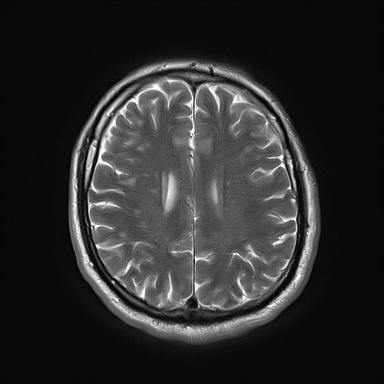

Petit rappel: L’IRM permet de

visualiser et localiser précisément les plaques

aussi bien dans le cerveau que dans la moelle épinière. Selon

les séquences utilisées, elles apparaissent blanches (en terme technique,on parle “d’hyper signaux”) ou

noires (“hypo signaux”).

Mes scanners IRM (imagerie par résonance magnétique)

(images au hasard : ne connaissant

pas l'interprétation)